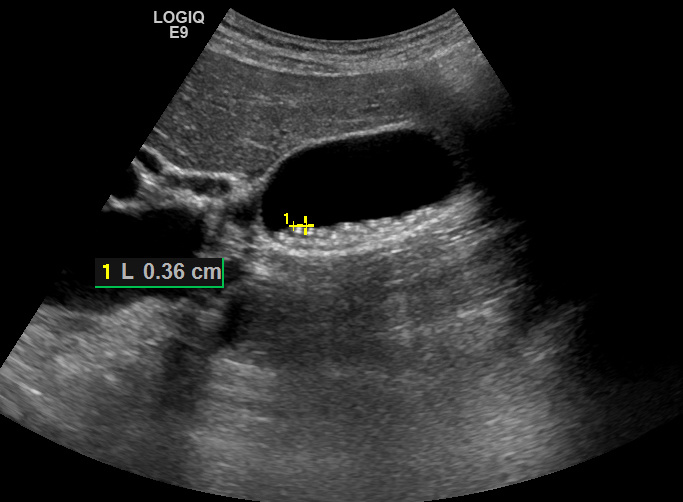

Пациентка 55 лет обратилась для ультразвукового исследования по направлению хирурга для оценки состояния желчных путей. О наличии камней в желчном пузыре осведомлена. На момент исследования жалоб не предъявляет.

При ультразвуковом исследовании в желчном пузыре определяются множественные конкременты (несколько десятков), размер которых не превышает 4 мм.

Рис. 01. Мелкие камни в желчном пузыре.

Размер камней не превышает 4 мм, дистальные акустические тени очень бледные. При попытке исследования в режиме ЦДК отмечаются единичные участки "мерцающего" артефакта.